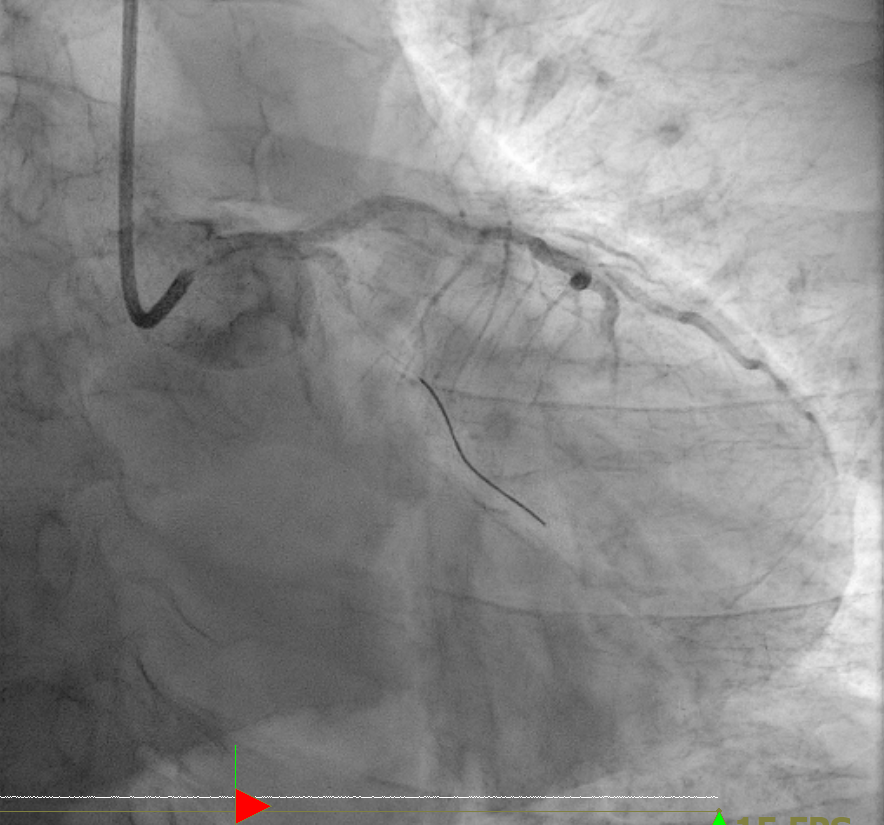

1번 영상에서 오른쪽으로 길게 뻗어있는 LAD(left anterior descending artery)의 모습과 근위부(proximal part)에서 막혀 있는 LCX(left circumflex artery)의 모습을 확인할 수 있다.

2~3번 영상에서는 막힌 LCX를 카테터를 통과시키고 thrombectomy를 하여 혈류가 어느 정도 나타난 상태이다.

4번에서는 다시 ballooning, stent insertion을 하는 모습이고

5번에서는 최종적으로 혈류가 회복된 모습을 보여주고 있다.

6번은 RCA(right coronary artery)의 모습을 보여주고 있다.

관상동맥 조영술 (Coronary angiography, CAG) 결과

- LM: OK

- LAD, prox. to mid, diffuse, 30-40% stenosis

Big D1, prox, diffuse, 60% stenosis

- LCX, prox. total occlusion -> thrombectomy ->No RS

- RCA, prox.to distal, diffuse, tandem, 30-40% stenosis